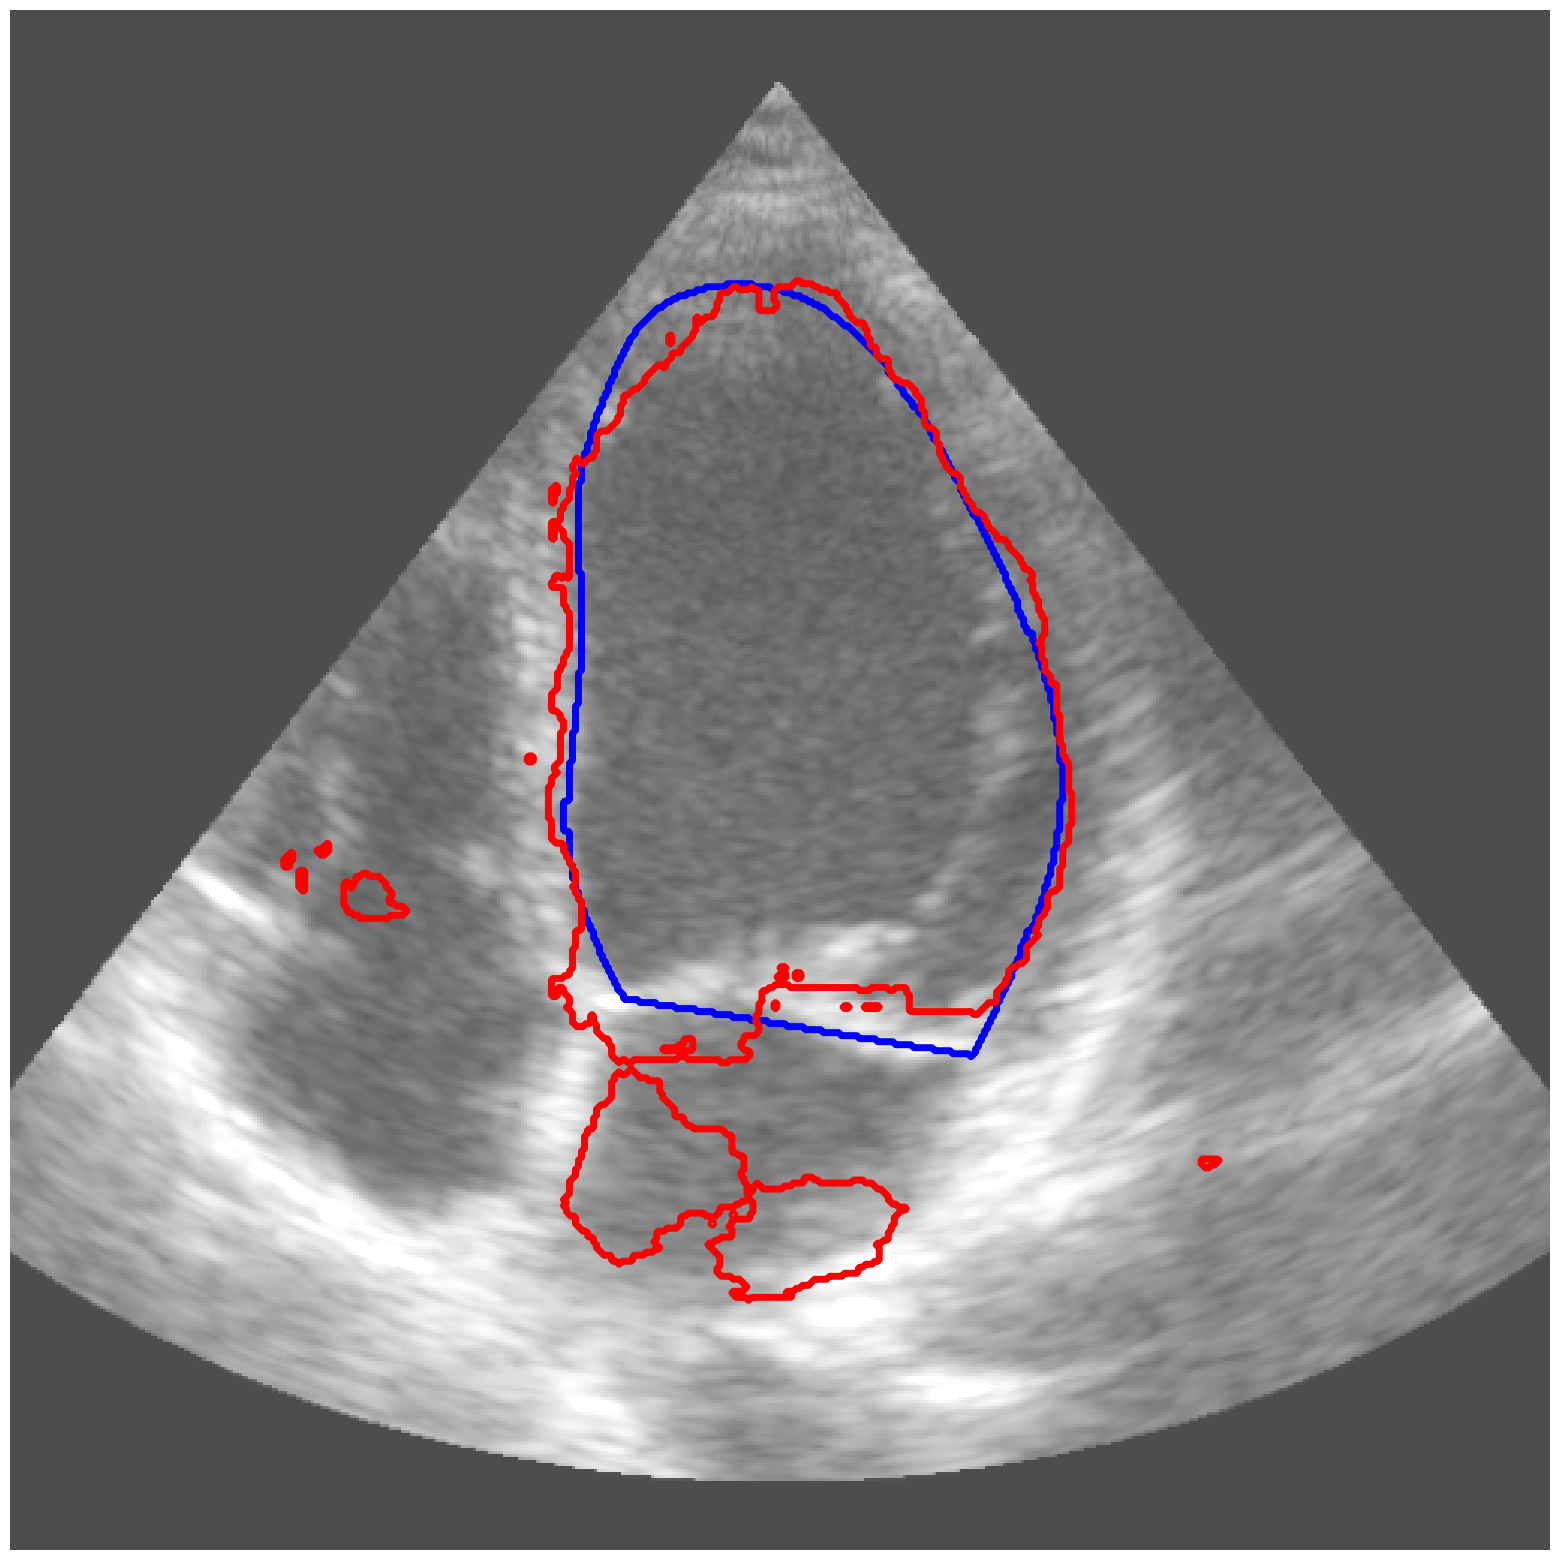

|

ACDC-RV |

![]() |

CAMUS |

| (a) Original pred. | b) Consema | ——— c) Standard CRC ——— | ——— d) RW-CP (Ours) ——— | |||

Visually, we observe in Fig. 1 that RW-CP is able to produce prediction sets much closer to the ground-truth than standard CRC or Consema. Our approach is even able to remove small over-segmentated areas, whereas methods such as Consema can only increase the size of the prediction set, even when the segmentation model produced false positives.

We hypothesize that the performance of RW-CP stems from its pre-processing step on probabilities, which mitigates the overconfidence commonly observed in deep learning segmentation models [16]. Their raw softmax probabilities are often skewed towards either 0 or 1 (see Fig. 1.c). This overconfidence compresses the effective range of possible values for the empirical threshold used in Conformal Risk Control, making the final prediction mask extremely sensitive to small fluctuations in . On the contrary, by first applying a diffusion process, the pixel-wise probabilities become more varied and less polarized (as shown in Fig. 1.d). This broadened distribution stabilizes the empirical during calibration, leading to a more robust and tighter prediction set, which translates to better overall segmentation metrics